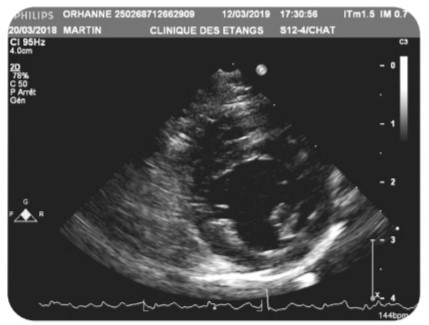

La Cardiomyopathie Hypertrophique Féline (HCM)

Cette maladie peut être diagnostiquée soit par la réalisation de test ADN, soit par échographie.

Le test ADN va déceler si le chat porte ou non le gène responsable de la maladie. C’est une transmission autosomique dominante, le chat hétérozygote porteur d’un allèle muté du gène PKD1 noté (N/PKD1) développera une PKD.

Toutefois certains chats homozygotes sains (non porteur du gène muté) pourront développer une PKD non liée à la mutation du gène PKD1. Il est donc recommandé de réaliser des échographies rénales qui recherchent la présence clinique de Kystes quelque soit leurs origines.